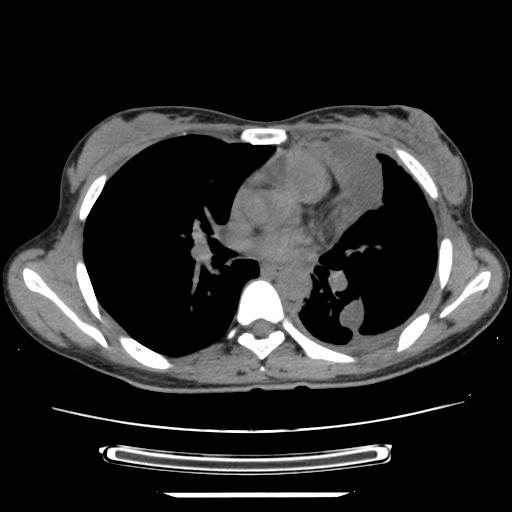

女,29岁,胸部不适,在外院胸片提示胸腔积液,到我院ct检查。

纵膈窗

左侧纵隔胸膜包裹性积液、左侧胸腔积液、胸膜肥厚粘莲,考虑结核性胸膜炎

左肺上叶不张,左侧胸水,叶间裂积液,纵隔淋巴结,脾脏钙化,考虑左肺上叶支气管内膜结核,结核性胸膜炎,脾结核

支持两肺继发性肺结核,左侧胸膜腔包裹性积液、胸膜肥厚,脾内多发钙化(结核钙化)。

支持 两肺继发性肺结核,左侧胸膜腔包裹性积液、胸膜肥厚;脾内多发钙化(结核钙化)。